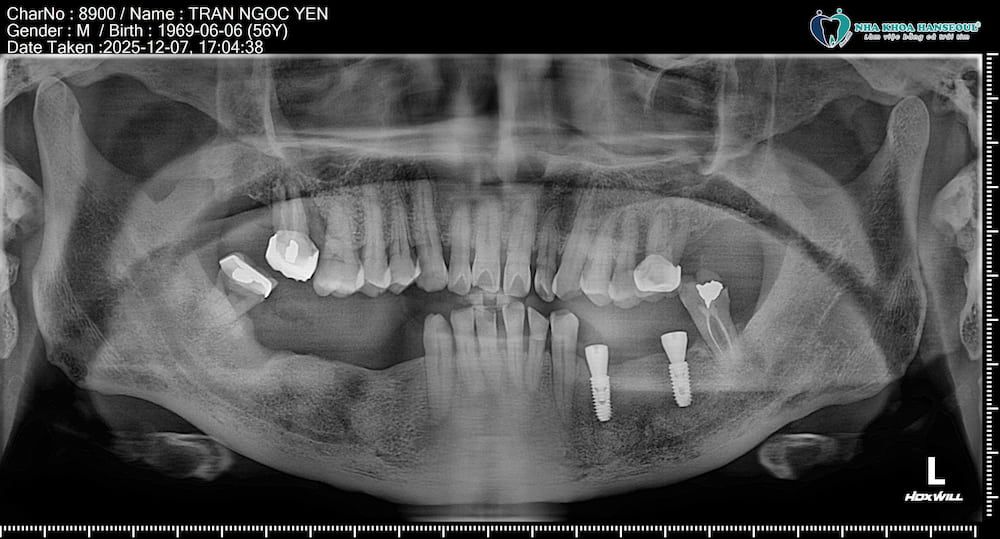

Sau khi chụp CT Conebeam và đánh giá toàn bộ cấu trúc xương hàm, bác sĩ đưa ra phương án điều trị tối ưu: cấy 5 trụ Implant Osstem SA tại các vị trí 34, 36, 44, 46, 47. 2 răng 34, 36 sẽ được cấy trước và sau 1 tuần sẽ cấy tiếp 3 trụ còn lại. Sau khi tích hợp xương ổn định, khách hàng sẽ được lắp răng sứ hoàn thiện.

2 trụ implant vị trí răng 34 và 36 được cấy trước. Người bệnh có trải nghiệm nhẹ nhàng, không đau.